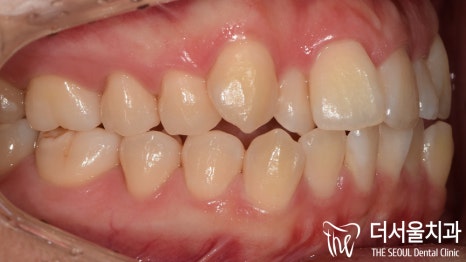

구내 포토를 봤을 때에 제가 표시를 해두었습니다.

치아들의 ‘배열’ 을 볼 수 있는데

알파벳 ‘U’자 형태가 아닌 삐뚤빼뚤 되어있는

총생(크라우딩, Crowding)이 되어있죠?

또한, 윗니는 앞으로

뻐드러져 있는 것을 볼 수 있습니다.

정면에서 봤을 땐,

정중심선[미드라인, mid line]이

맞지 않는 것이 확인 되는 동시에

측절치는 왜소치 경향이 있었고

송곳니는 덧니가 관찰되고 있습니다.

측면에서 바라보니,

앞으로 더 많이 뻐드러져 있는 것이 확인이 되죠?

이런 증세들 때문에

입술이 튀어나온 것 처럼 보여지게 되는 겁니다.